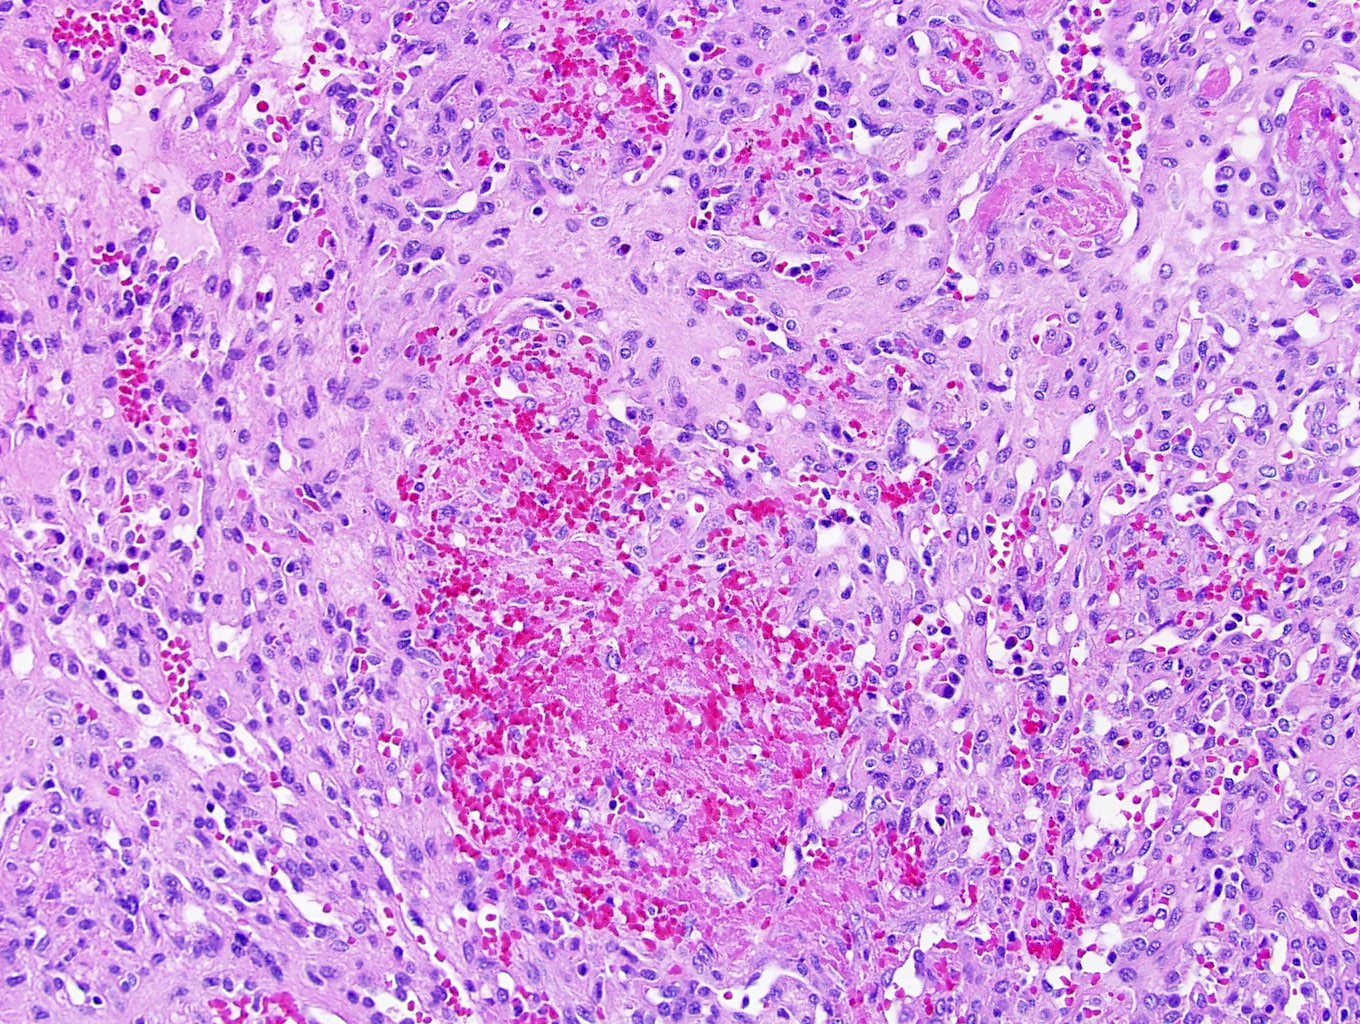

Microscopic (histologic) description

- Circumscribed, unencapsulated proliferation of irregular, blood filled vascular spaces lined by a single layer of endothelial cells

- May or may not show lobular growth pattern with large feeding vessels at periphery (Virchows Arch 2012;461:669)

- Multiple subtypes:

- Capillary: more common, characterized by slit-like vascular spaces

- Cavernous: characterized by dilated vessels

- Mixed: features of both capillary and cavernous

- Anastomosing hemangioma (variant of capillary)

- Anastomosing hemangioma (AH):

- Capillary sized sinusoidal vessels with anastomotic arrangement

- Scattered hobnail endothelial cells

- Extramedullary hematopoiesis, fibrin thrombi, extensive perirenal fat entrapment, intravascular growth and mast cells may be seen (Histopathology 2014;65:309)

- Cytologic atypia and mitotic activity rare

- Regressive changes, including hyalinization, cystic changes and fatty overgrowth (Histopathology 2014;65:309)

Microscopic (histologic) images